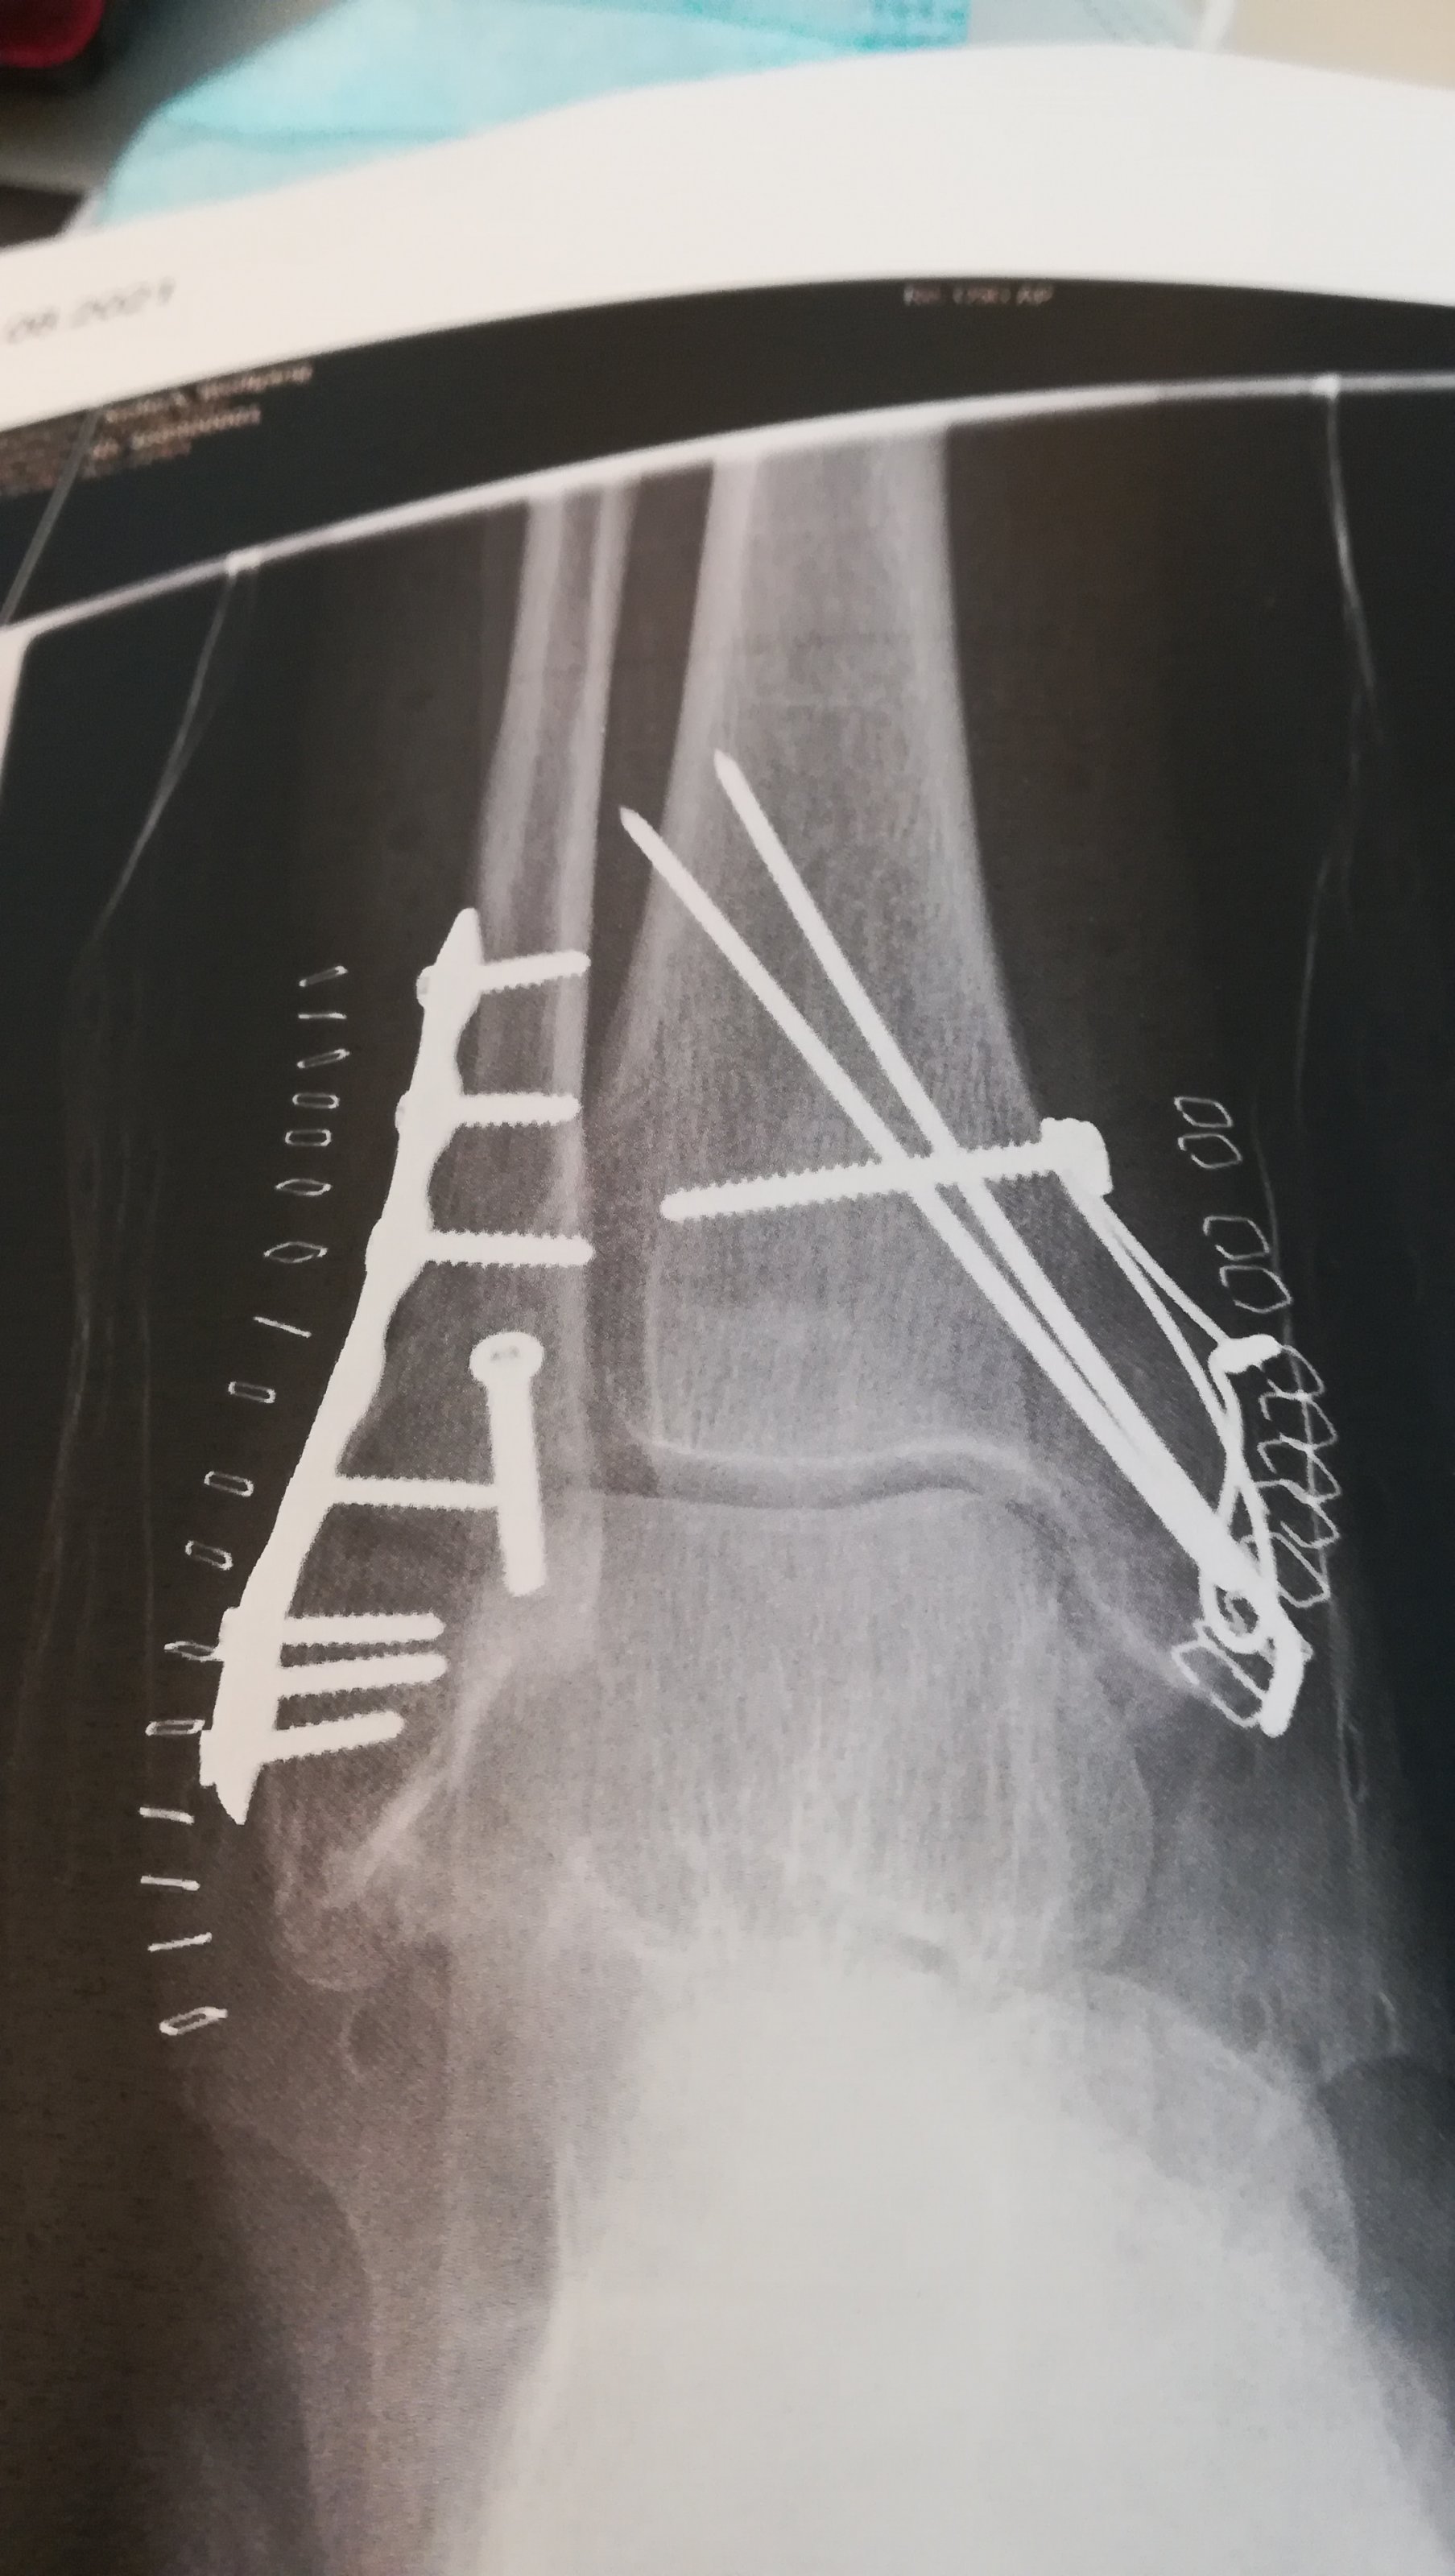

Ich drücke dir die Daumen dass alles gut geht, mir haben sie gerade zur Sicherung des Ganges einen Stock verpasst! nach genau der gleichen Aktion die jetzt zwei Jahre zurückliegt.Gestern wurde 8,5 Wochen nach der OP (Knöchel Bruch und Syndesmoseband gerissen) die Stellschraube entfernt. Kann jetzt langsam die Belastung steigern und hoffe bald wieder auf der GS zu sitzen. Es geht aufwärts![]()

Besser ist dass man haut da richtig rein, aber bei mir war das ein bisschen komplizierter ich hatte mir auf dem Weg zwischen Unfall und es ist alles wieder gut einen MSRA Keim eingehandelt, der ein zweimaliges nach operieren erforderlich machte und dadurch alles sehr viel komplizierter machte. Aber worüber ich mich bis heute freue ist, der Fuß ist noch da!Oh, das tut mir leid für dich. Da muss ich mich wohl bei der Physio richtig anstrengen.

was für eine Scheiße, Mann. Sieh trotzdem zu, dass Du in Gang bleibst, sonst reißt das ein. Alles Gute DirBesser ist dass man haut da richtig rein, aber bei mir war das ein bisschen komplizierter ich hatte mir auf dem Weg zwischen Unfall und es ist alles wieder gut einen MSRA Keim eingehandelt, der ein zweimaliges nach operieren erforderlich machte und dadurch alles sehr viel komplizierter machte. Aber worüber ich mich bis heute freue ist, der Fuß ist noch da!